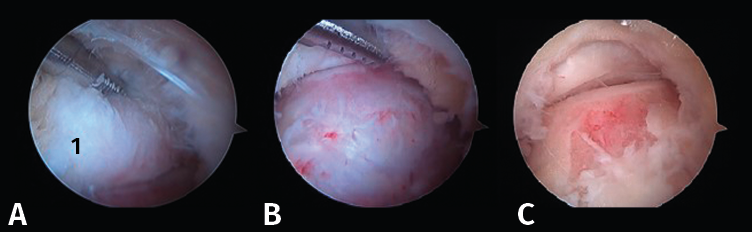

Figura 5. A: resección de tejidos blandos en la parte superior del proceso posterolateral del astrágalo (1); B y C: realización de la artrotomía tibioastragalina posterior siguiendo una dirección horizontal.

- Segundo paso: eliminar el tejido blando en la parte superior del PPA. La ventana del sinoviotomo se gira 90° para apoyarse sobre la parte superior del PPA. Con ello, se realiza la artrotomía tibioastragalina y se escinde la cápsula hipertrófica de la articulación posterior. Es importante realizar movimientos en plano horizontal para preservar la continuidad del ligamento intermaleolar y evitar una artrotomía de trazo vertical que podría seccionar inadvertidamente dicho ligamento (Figuras 5 A, B y C).